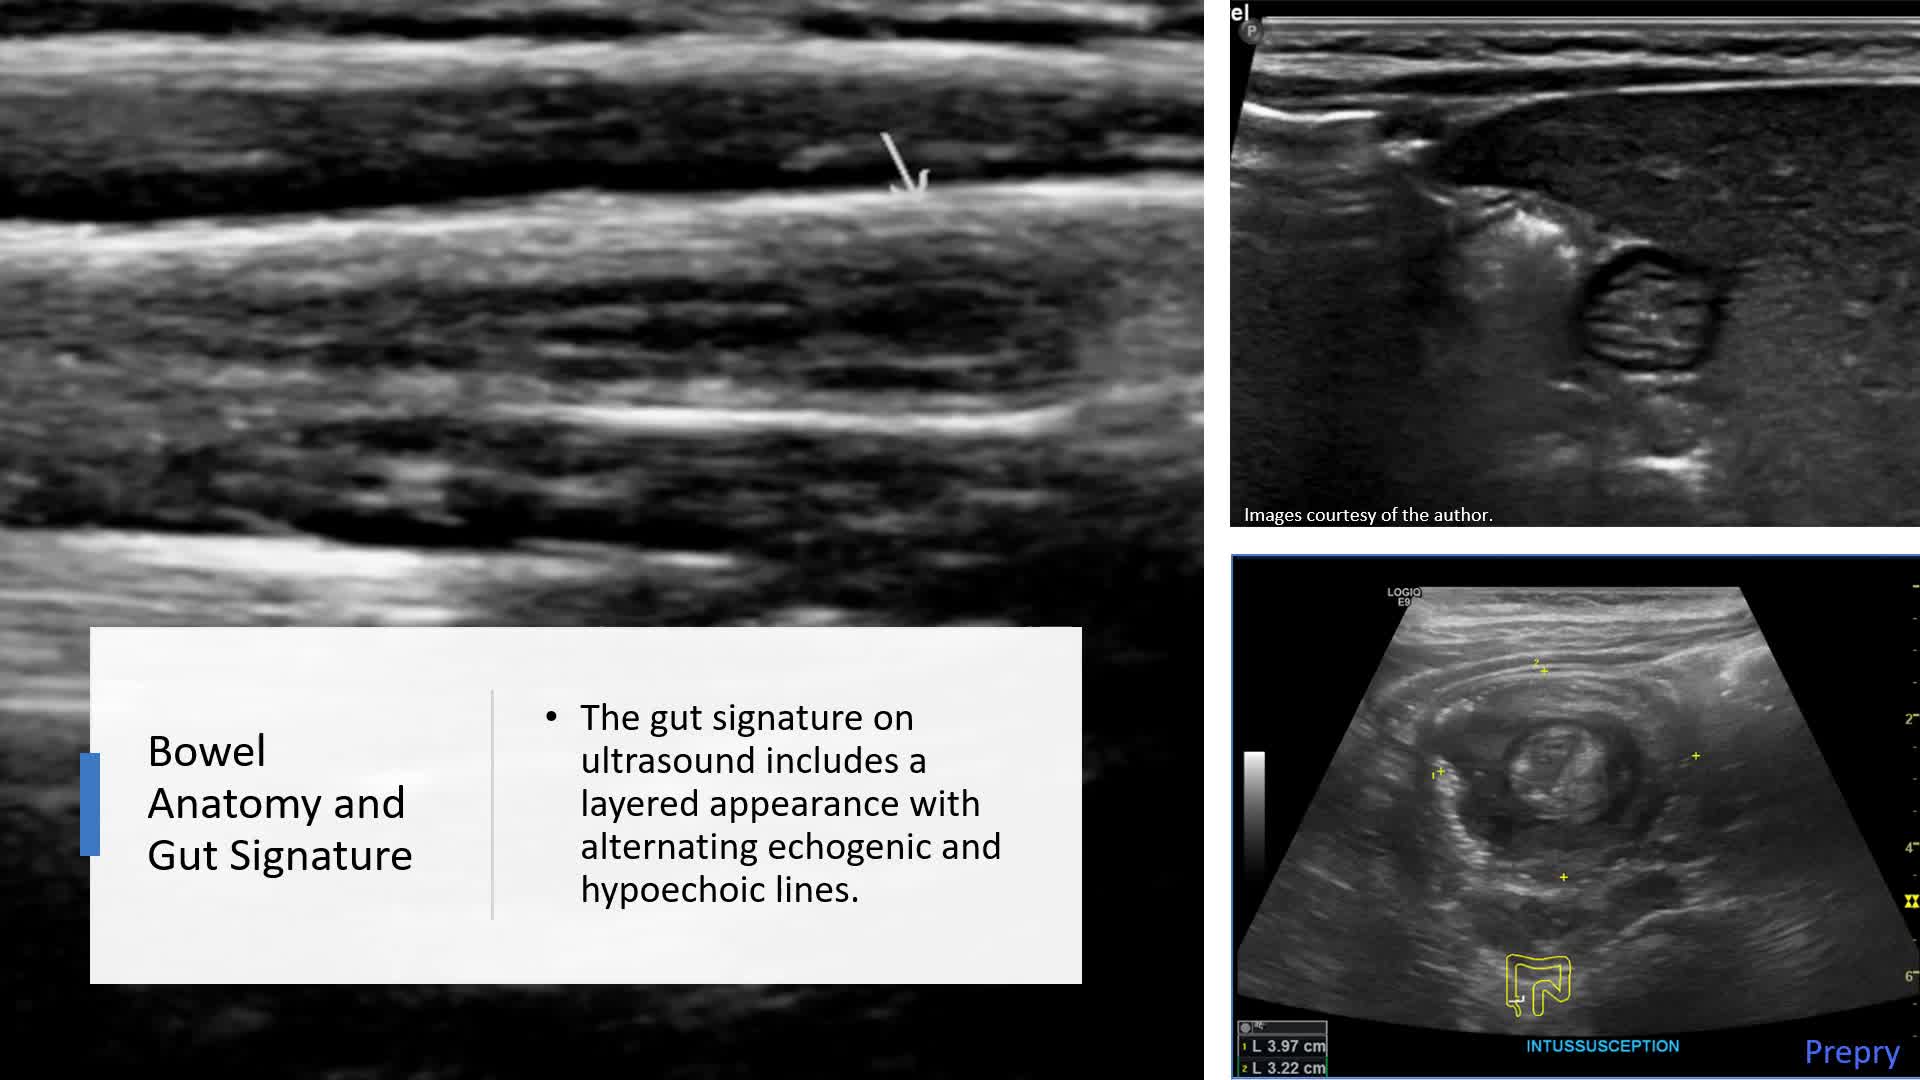

Biliary System and Pancreas - Part 1: Biliary System

Biliary System